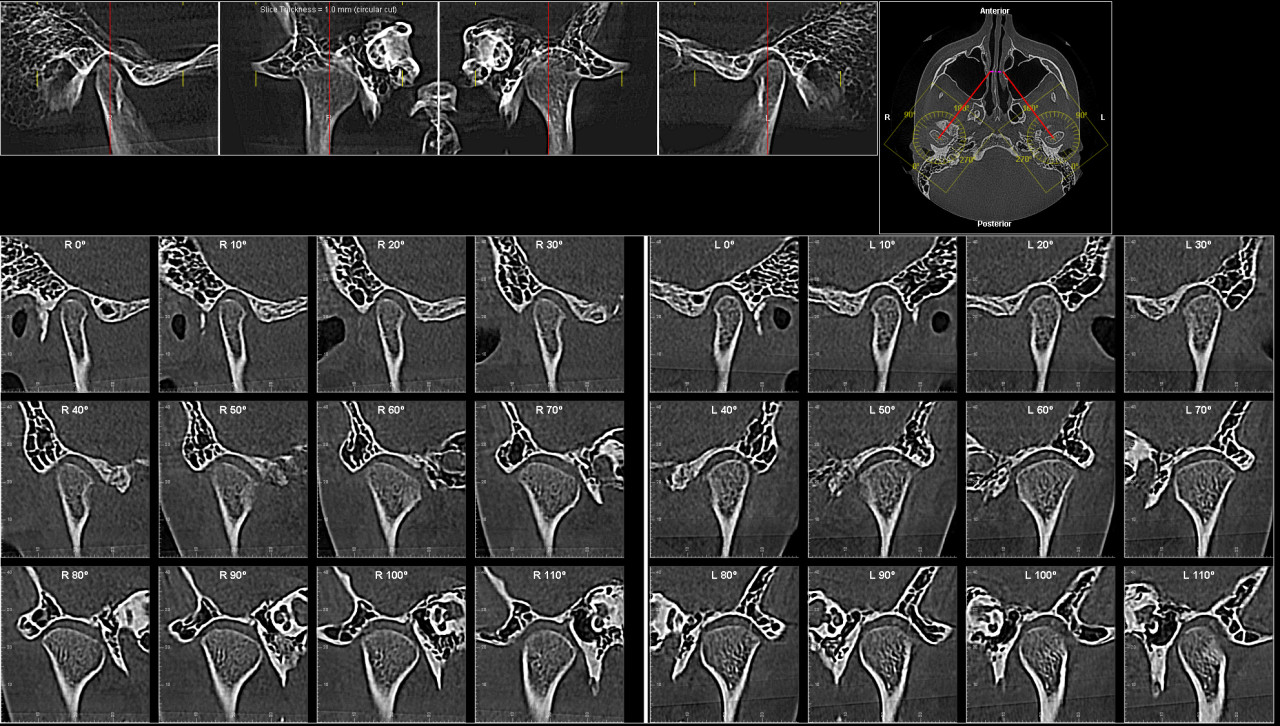

Здравствуйте. По вашим КТ видно выраженную скученность, узкую верхнюю дугу и проблему с нижней пятёркой, один зачаток расположен горизонтально, второй отсутствует. При такой анатомии ортодонтическое лечение без удаления зубов часто приводит к нестабильному результату или чрезмерному расширению, которое челюсть просто не удержит.

По снимкам можно сказать следующее:

- верхние резцы действительно выдвинуты вперёд, места мало

- симметрия зубных рядов нарушена из-за отсутствия одной нижней пятёрки

- восьмёрки по расположению не выполнят функцию премоляров

-вытяжение горизонтально лежащего зачатка пятёрки технически возможно, но долго, сложно и не всегда удачно

-при сохранении всех зубов есть риск рецидива и ухудшения профиля лица

Поэтому вариант с удалением верхних пятёрок и проблемной нижней пятёрки выглядит более предсказуемым с точки зрения симметрии и стабильности результата. Это не значит, что другой план неверен, но он более рискованный и требует очень опытного врача и долгого лечения.

Большое спасибо за Ваше мнение! Есть еще такие снимки

По этим снимкам видно, что суставы и положение нижней челюсти также не дают достаточного пространства для безопасного расширения дуг. При такой анатомии лечение без удаления зубов может привести к перегрузке сустава и рецидиву. Поэтому удаление отдельных премоляров и проблемной нижней пятёрки остаётся более надёжным вариантом для стабильного результата.